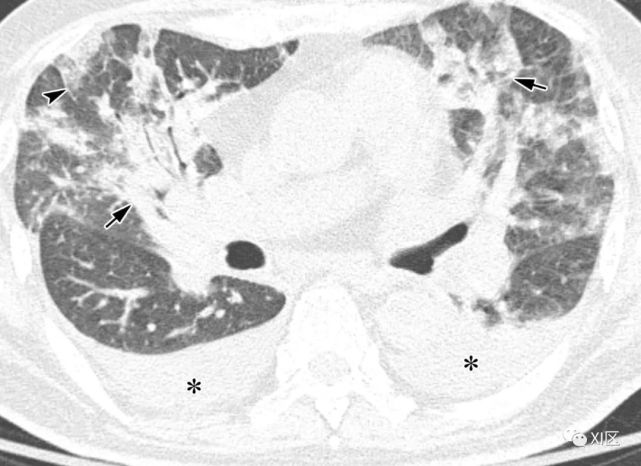

图13 63岁的男子,原发性中枢神经系统淋巴瘤化疗后合并发热,诊断为人博卡病毒肺炎

(上)胸部X线片显示两肺均弥漫性不规则斑块状实变(箭)和GGO。在同一天获得的轴位薄层(1mm)胸部CT图像显示,沿着支气管血管束和肺部周边区域出现不规则的斑块状实变(箭),支气管壁增厚,小叶间隔增厚 (箭头),伴有少量双侧胸腔积液(*)。

Koo H J , Lim S , Choe J , et al. Radiographic and CT Features of Viral Pneumonia[J]. Radiographics, 2018, 38(3):719-739.